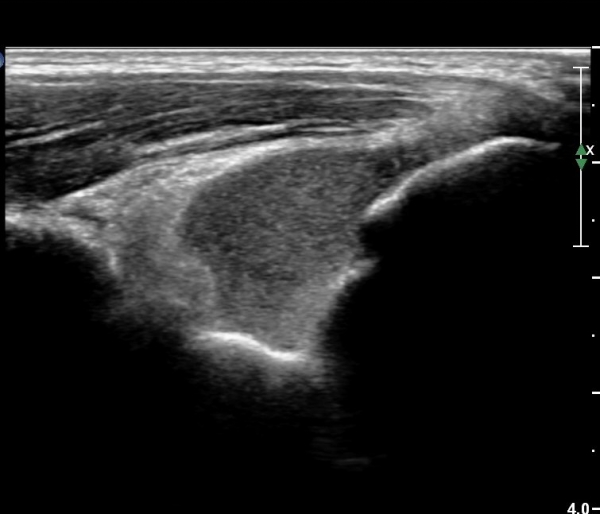

ÁÖµÎ¿Í Á¾´Ü¸é°Ë»ç¿Í Ⱦ´Ü¸é°Ë»ç¿¡¼­ ÁֵοͿ¡ ÀÌÁúÀû¿¡ÄÚ¸¦ º¸ÀÌ´Â

´Ù·®ÀÇ ¼ö¾×Àú·ù°¡ °üÂûµÊ(»çÁø 5, 6).